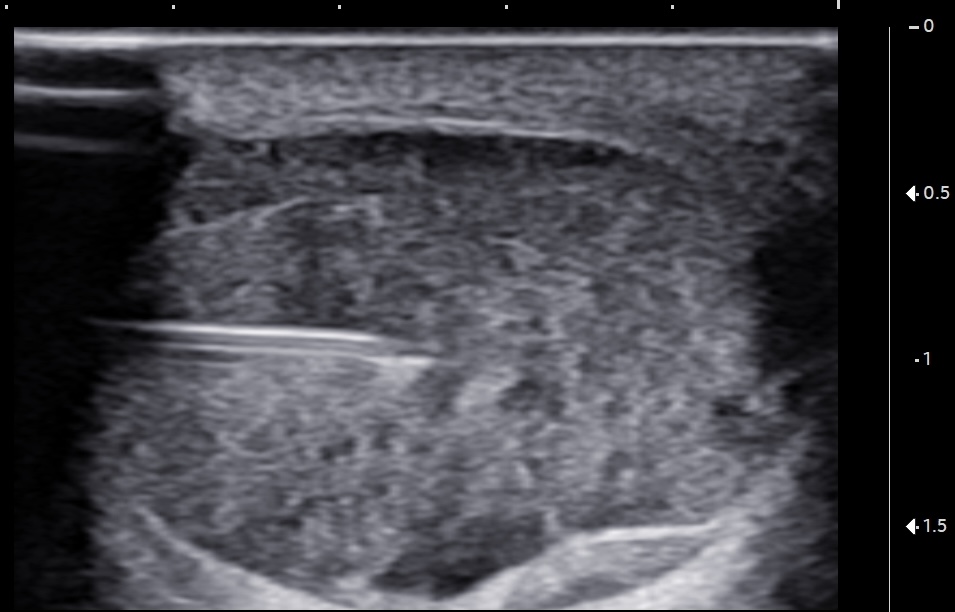

Unlabeled short-axis ultrasound image of the midportion Achilles tendon showing the 22-gauge, 1.5-inch needle advancing with a lateral-to-medial approach through the tendon before injecting the bone marrow concentrate.